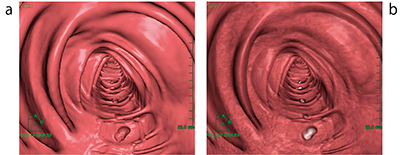

図1 経路探索画面

次に,仮想内視鏡モードで観察していく。比較読影モードであれば,仰臥位,腹臥位ともほぼ同じ位置で表示されるので比較しやすい。片方の体位で病変らしきものがある場合に,もう片体位で移動していれば残渣と考え,同じ位置にあれば病変が疑われる(図2)。

図2 比較読影モード

仰臥位(a),腹臥位(b)とも同じ位置に隆起性病変が見られ,残渣ではない(CT値40HU)。